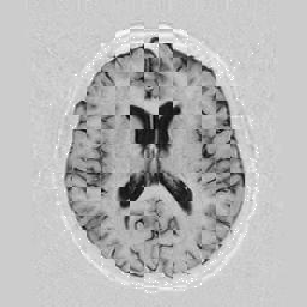

Another larger group of experiments enabled me to study the effects of multi-scale NRR. The results are shown in the form of chequerboard images in Figure [*]. In terms of resolution levels, higher numbers mean that the images are coarser.

Figure: Multi-scale NRR (increasing resolution). From left to right, top then bottom:before NRR; after 5 iterations of NRR at level 2 (higher is coarser); after another 5 iterations of NRR at level 1.